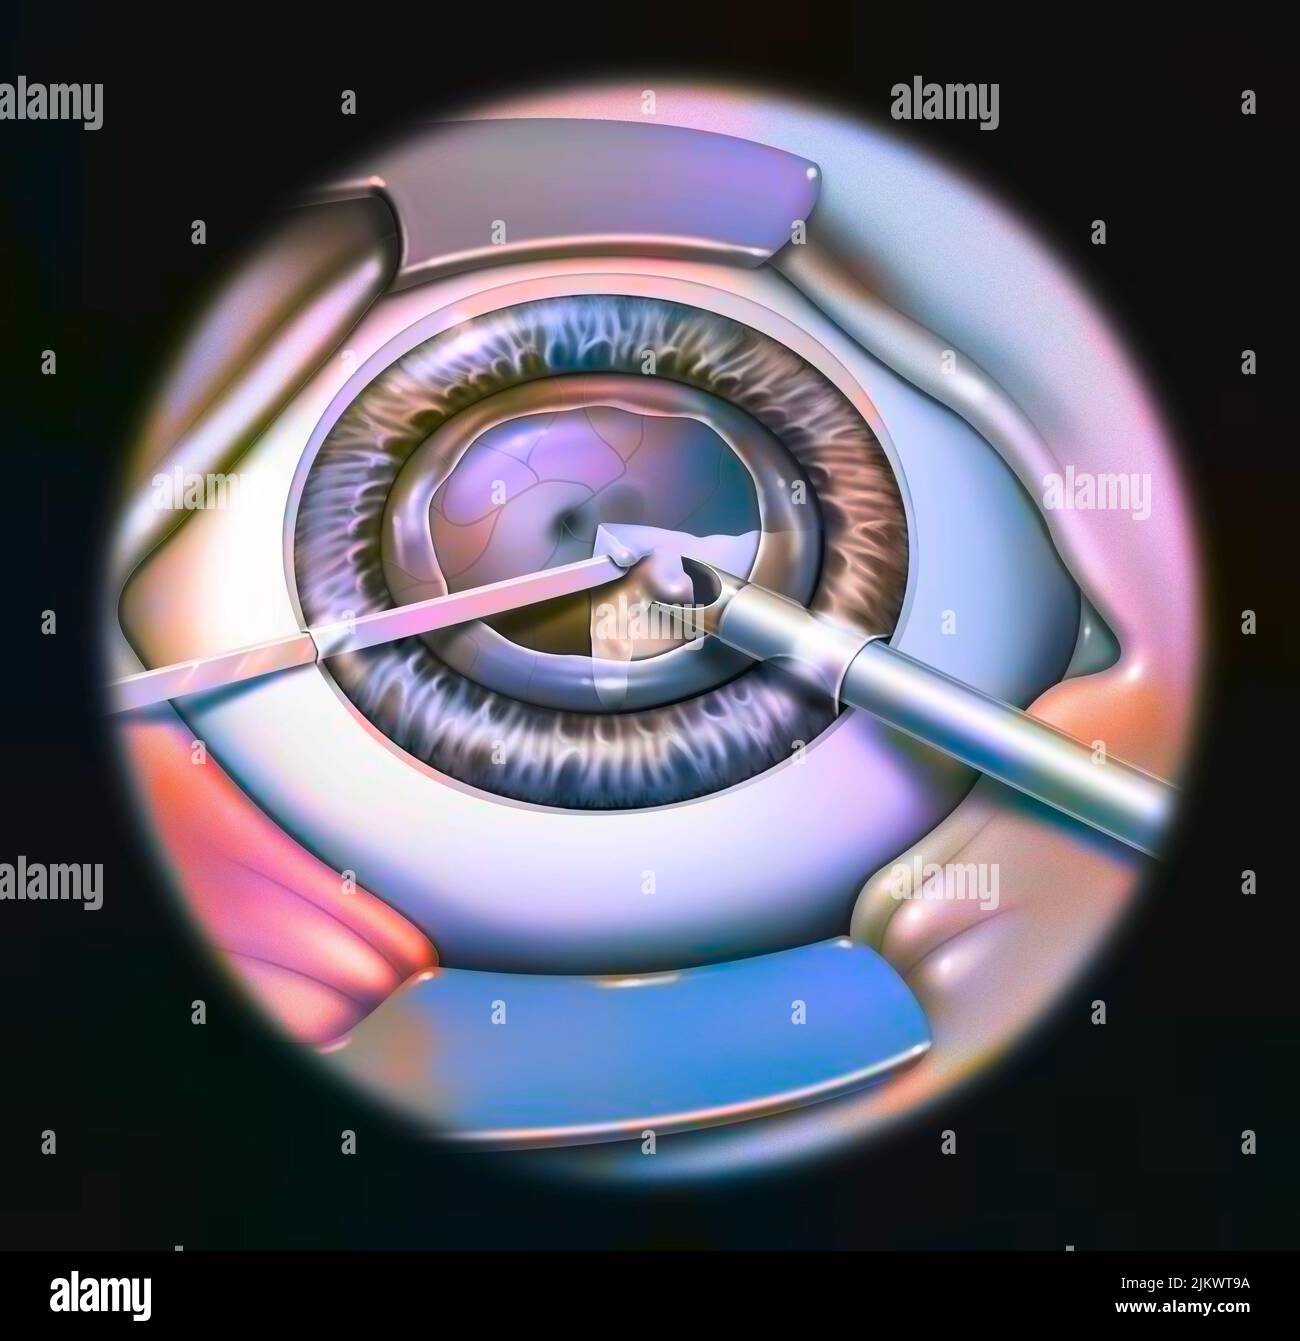

RF2JKWT9A–Oeil, cataracte, phacoémulsification - étape 2: Consiste à casser la lentille avec une sonde.